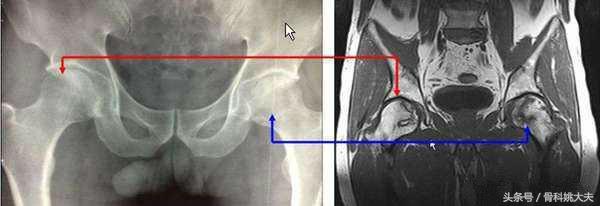

一照片,竟然股骨头坏死了

片子上看股骨头边缘已经发生严重的改变,可才40岁啊,做了关节置换还是有些不方便,而且他髋关节疼痛并不剧烈,还能正常行走…